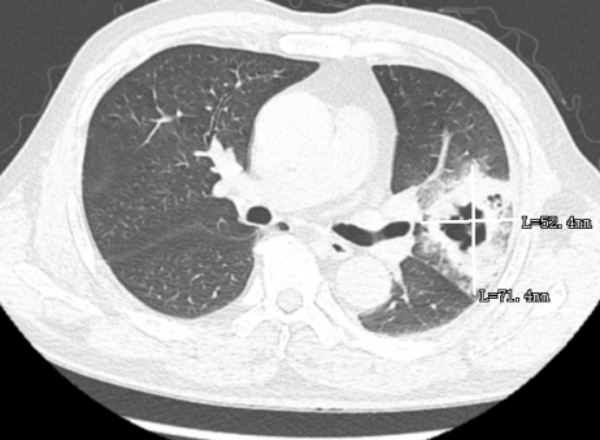

通過氣管鏡檢查,發(fā)現(xiàn)患者的肺部中有許多膿痰,氣管鏡協(xié)助將膿痰吸引干凈,并將膿痰送檢病原體靶向測序,發(fā)現(xiàn)患者存在兩種鏈球菌的感染,最終醫(yī)生根據(jù)病原體靶向測序的結(jié)果進(jìn)行針對性用藥,患者便好轉(zhuǎn)了很多,后續(xù)的CT檢查中可以看到,6cm的病灶已縮小到2cm不到。

▲治療后